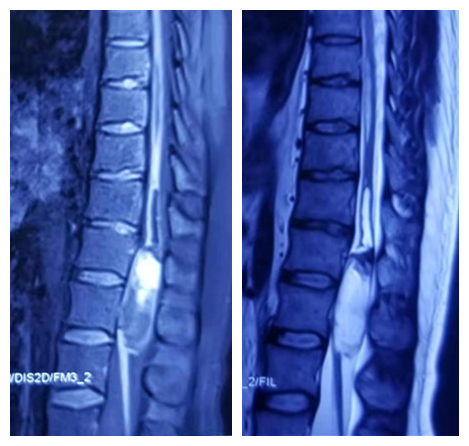

患者男性,25岁,因“腰背痛伴双下肢放散性疼痛、麻木、无力,大便障碍4个月,逐渐加重1个月”,及“椎管占位性病变”入院。核磁及强化检查等影像学显示胸11-腰1段椎管内脊髓圆锥处可见类圆形强化影,边缘呈环形高信号,内有不规则结节样强化,病灶纵形走形,范围约2.3cm×2.4cm×6.3cm,脊髓及马尾明显受压变形,胸8-12椎体水平脊髓中央管不均匀扩张(图片1)。

术前MRI表现